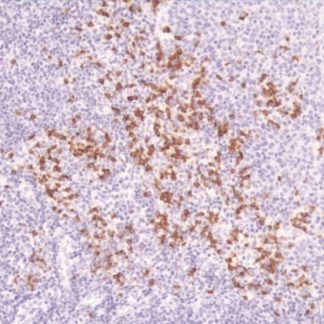

As a result, positive brown cytoplasmic staining strongly indicates a melanocytic origin.

- Clear brown cytoplasmic staining in positive cells

- Detection of malignant melanoma

- Identification of clear cell sarcoma and melanocytic nevi